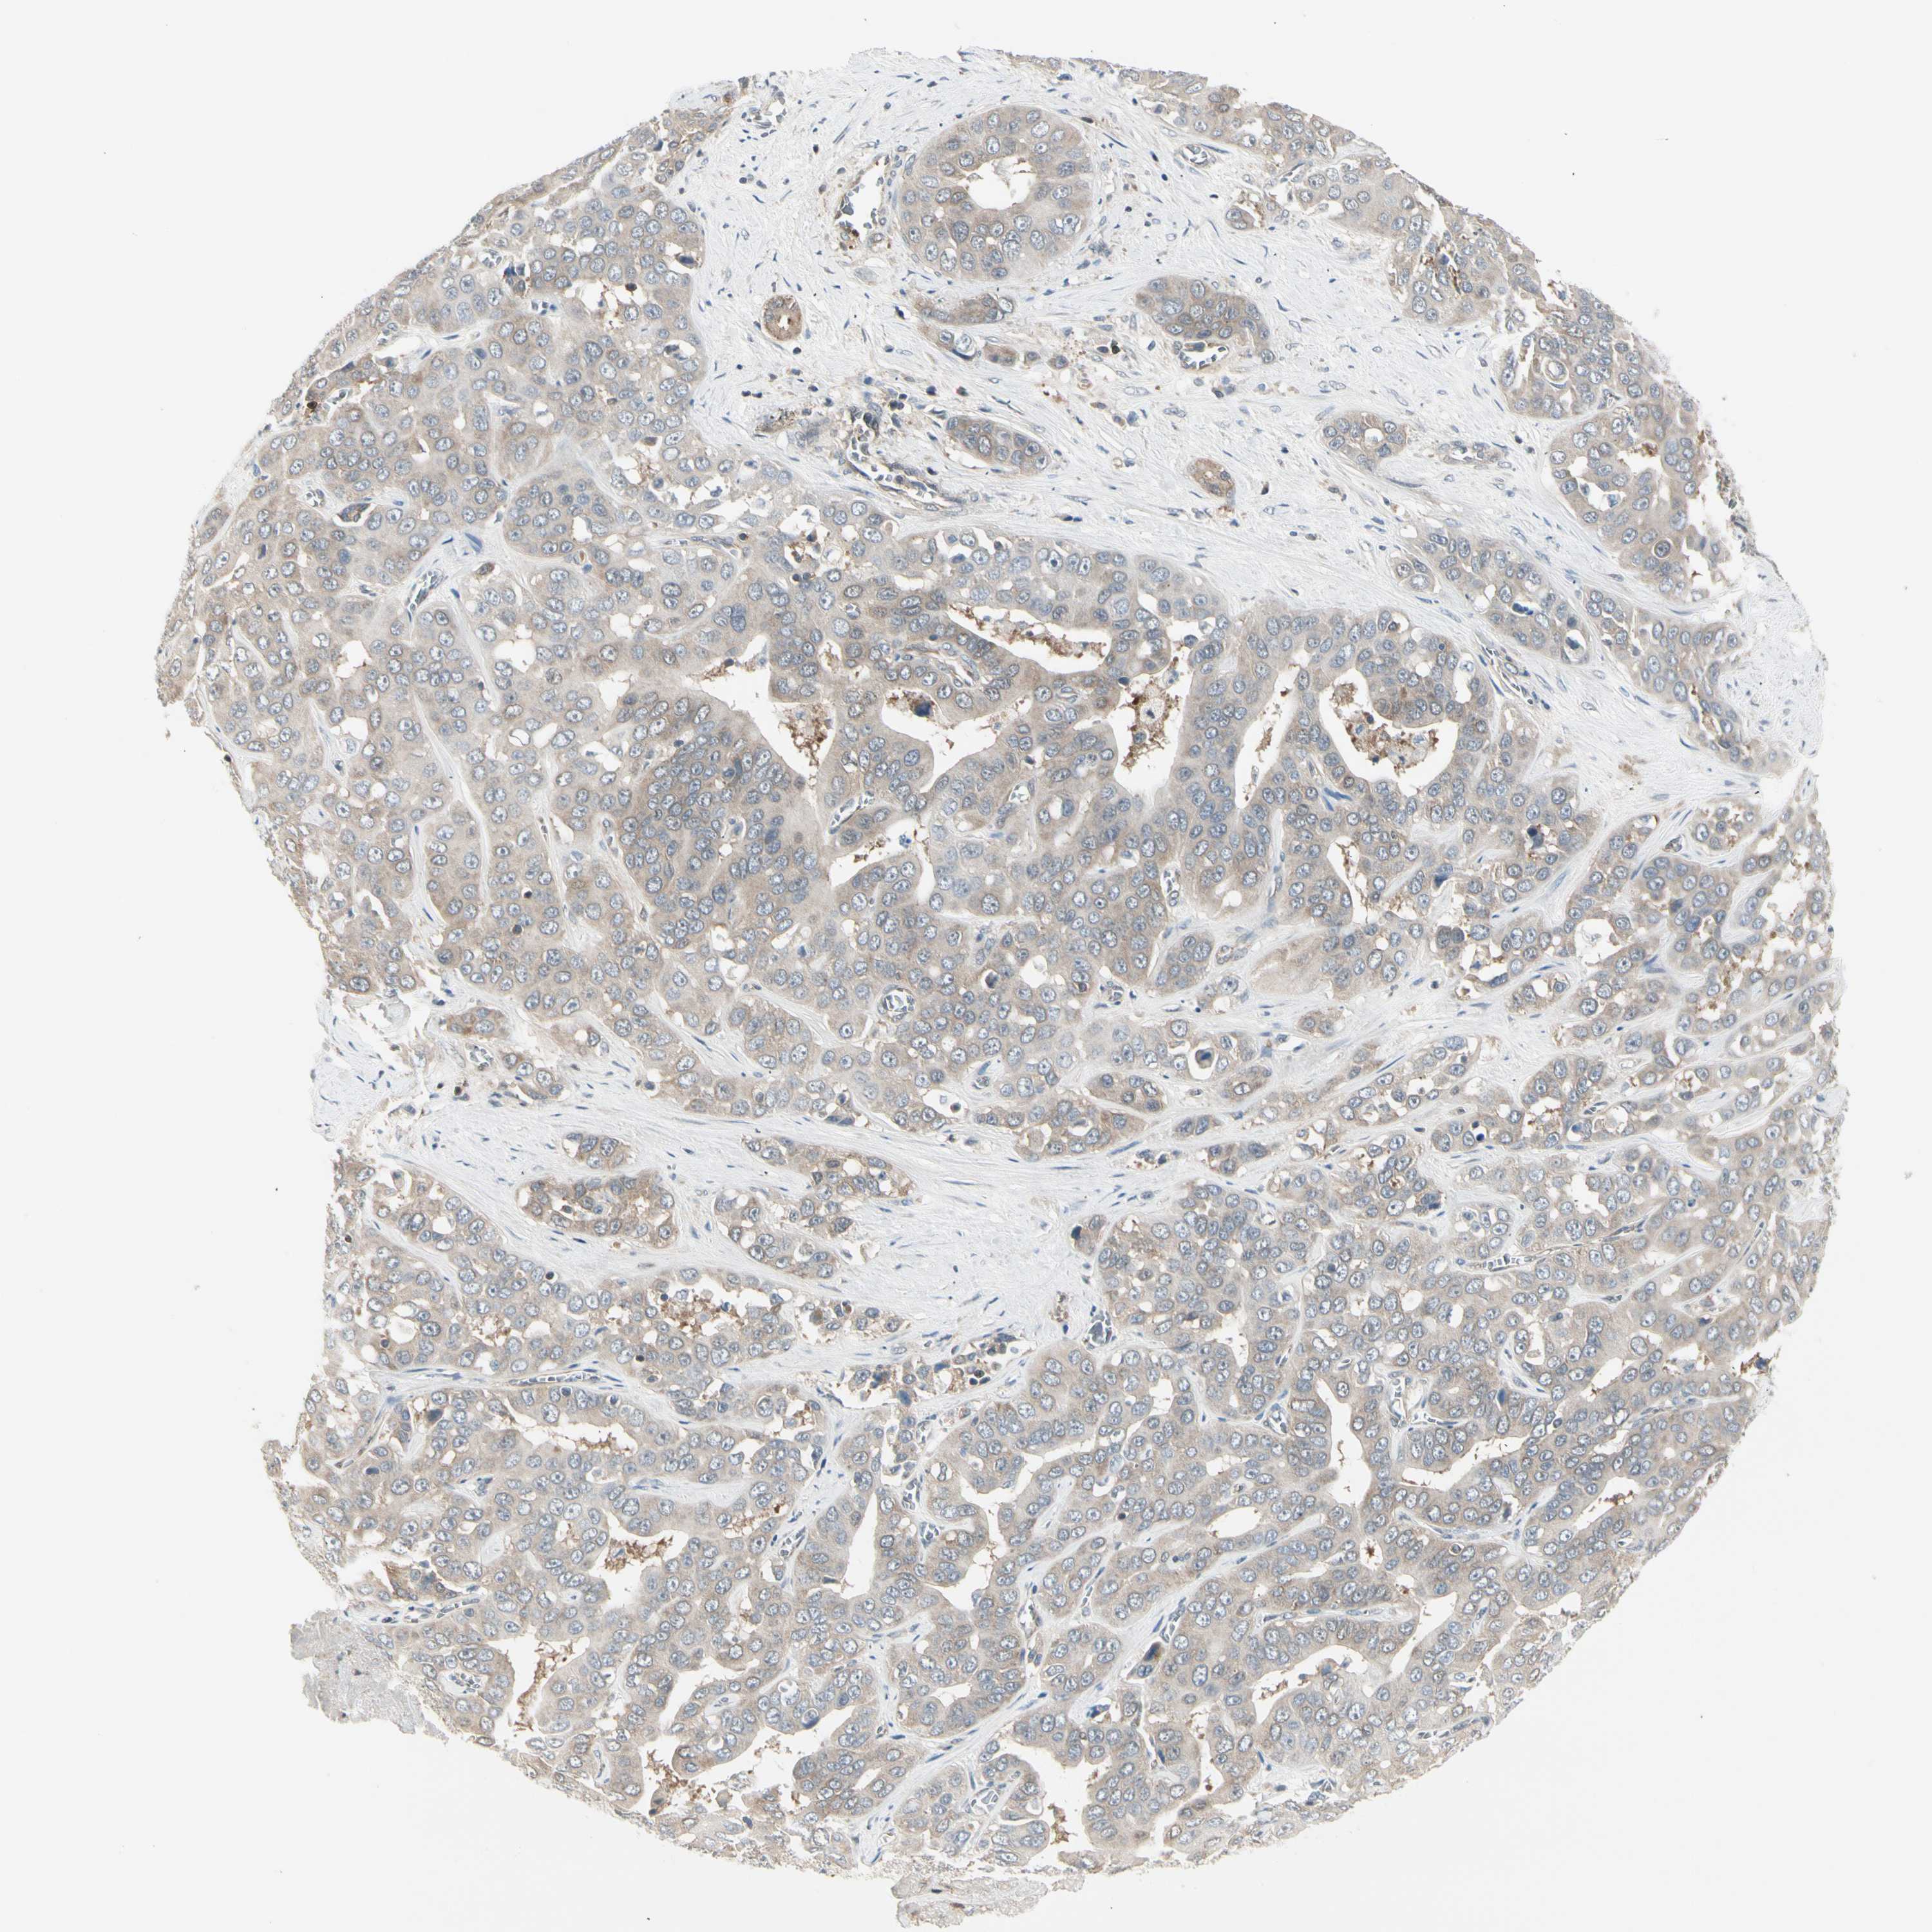

LIVER CANCER - Protein expressioni

A mouse-over function shows sample information and annotation data. Click on an image to view it in a full screen mode. Samples can be filtered based on level of antibody staining by selecting one or several of the following categories: high, medium, low and not detected. The assay and annotation is described here.

Note that samples used for immunohistochemistry by the Human Protein Atlas do not correspond to samples in the TCGA dataset.

Antibody stainingi

Antibody staining in the annotated cell types in the current human tissue is reported as not detected, low, medium, or high, based on conventional immunohistochemistry profiling in selected tissues. This score is based on the combination of the staining intensity and fraction of stained cells.

Each image is clickable and will lead to virtual microscopy that enables deeper exploration of all samples and also displays staining intensity scores, fraction scores and subcellular localization as well as patient and tissue information for each sample.

Antibody HPA008237

Antibody CAB017181

Staining

High

Medium

Low

Not detected

Intensity

Strong

Moderate

Weak

Negative

Quantity

>75%

75%-25%

<25%

None

Location

Nuclear

Cytoplasmic/membranous

Cytoplasmic/membranous,nuclear

Cholangiocarcinoma

Carcinoma, Hepatocellular, NOS